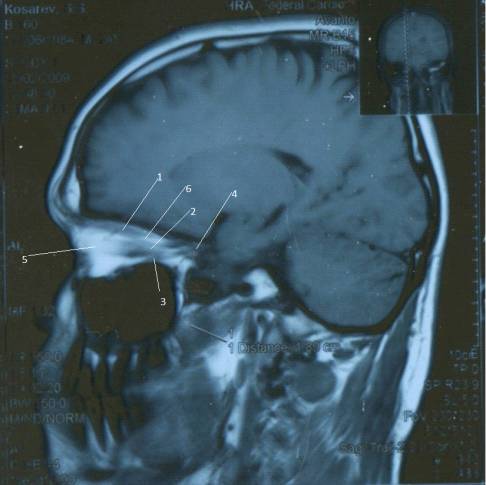

Рис. 5. МР-томограмма глаза в норме: 1 -

хрусталик; 2 - стекловидное тело глазного яблока; 3 - слезная железа; 4 -

зрительный нерв; 5 - ретробульбарное пространство; 6 - верхняя прямая мышца; 7

- внутренняя прямая мышца; 8 - наружная прямая мышца;9 - нижняя прямая мышца

Костные стенки глазниц дают выраженный

гипоинтенсивный сигнал на Т1-ВИ и на Т2-ВИ. Глазное яблоко состоит из оболочек

и оптической системы. Оболочки глазного яблока (склера, сосудистая оболочка и

сетчатка) визуализируются в виде четкой темной полоски на Т1-ВИ на Т2-ВИ,

окаймляющей глазное яблоко как единое целое. Из элементов оптической системы на

МР-томограммах видны передняя камера, хрусталик и стекловидное тело (см. рис.

5).

На Проекции Мт №1

визуализируются следующие

анатомические образования:

.Слезная железа - Glandula

lacrimalis

.Ретробульбарное пространство -

Spatium retrobulbar

3.Верхняя

прямая

мышца

- M. Rectus superior

.Глазное

яблоко

- Bulbus occuli